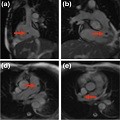

Prognostic value of novel imaging parameters derived from standard cardiovascular magnetic resonance

in high risk patients with systemic light chain amyloidosis

Nisha Arenja, et al.

Published on: 22 August 2019